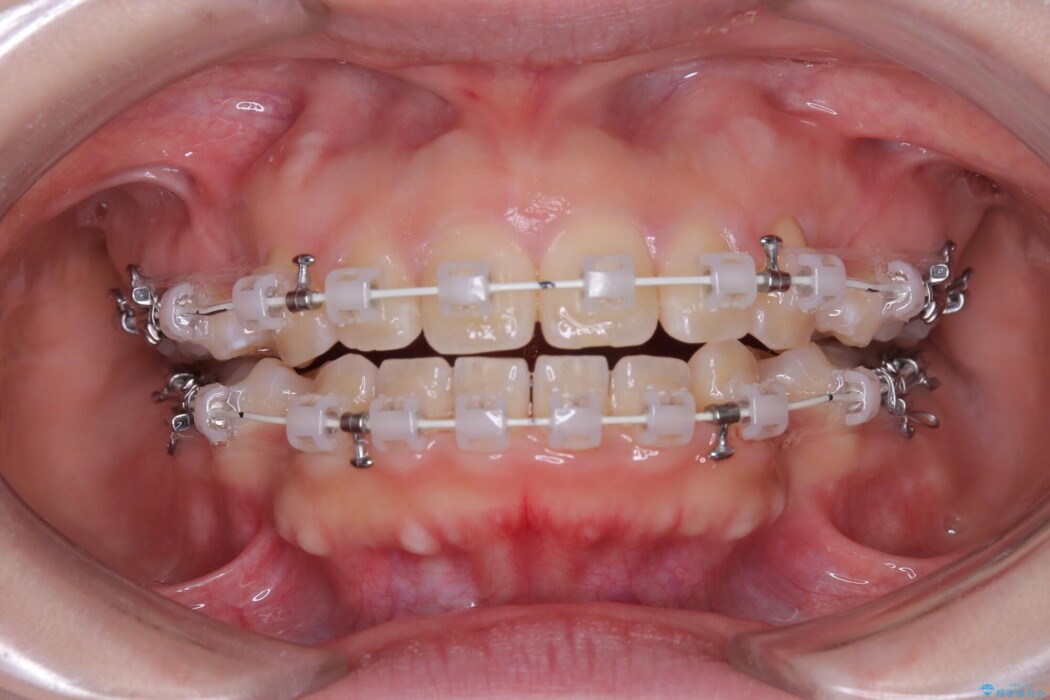

- 矯正装置:ワイヤー(審美装置)

矯正検査の結果、前歯が外側に強く倒れ込んでいる「唇側傾斜(しんそくけいしゃ)」が認められ、口元の突出感の原因になっていました。

この傾斜を根本から正し、前歯を十分に後方へ下げるスペースを確保するため、上下左右の4番を抜歯し、目立ちにくい審美ワイヤー装置にて治療を行うこととしました。

抜歯で得たスペースを活用し、大きく傾いた前歯の角度を修正しながら、ゆっくりと後方へ移動させていきました。

抜歯スペースが閉じるにつれて、唇側の圧迫感が解消され、口元のボリュームが自然に抑えられていきました。